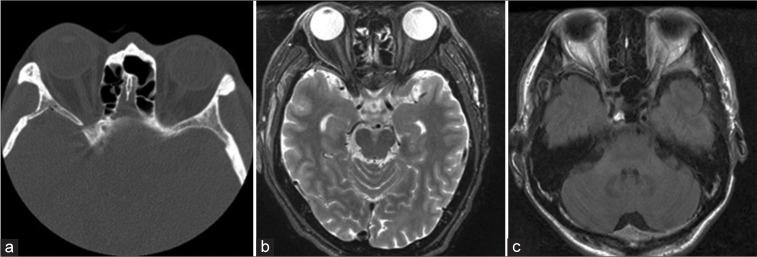

A 48-year-old man had fallen from a height of 7 m, striking his head. He immediately complained of right-eye blindness. He had no light perception and the direct light reflex disappeared from the right pupil, although there was no fracture or traumatic lesion on computed tomography and magnetic resonance imaging. Because the amplitude of the VEP with the right eye stimulation remained unchanged, we performed the right OCD. During surgical OCD, the amplitude and latency of VEP began to improve. Finally, the visual field improved in almost all directions, and eyesight improved to 0.2.

一名48岁男性从7米高处坠落,头部着地。他当即诉说右眼失明。右眼无光感,右瞳孔直接对光反射消失,尽管计算机断层扫描和磁共振成像未显示骨折或外伤性病变。由于刺激右眼时VEP波幅未变,我们实施了右侧OCD。手术OCD过程中,VEP波幅和潜伏期开始改善。最终,几乎所有方向的视野均有改善,视力提高到0.2。